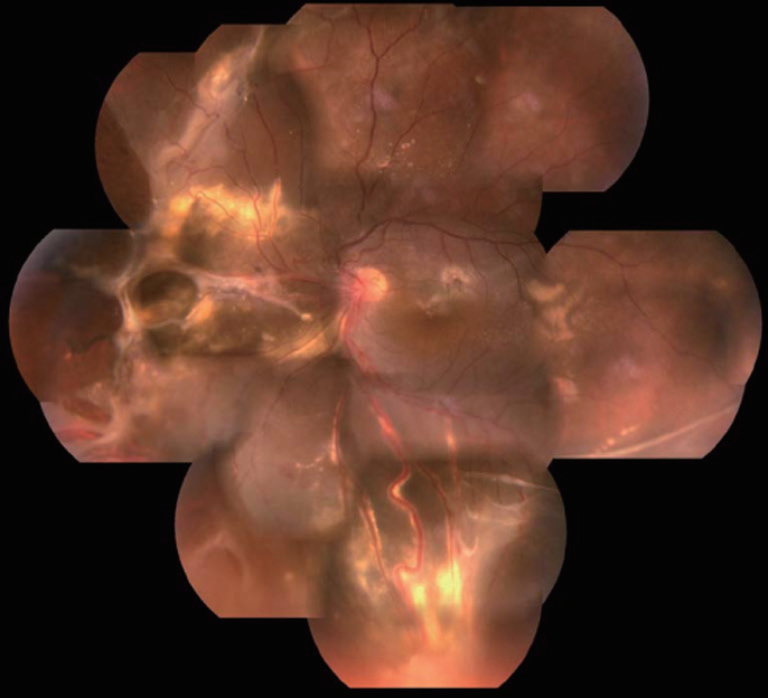

图2 眼底照片显示左眼鼻侧和下方周边部可见3个大的视网膜血管母细胞瘤(箭头),伴有扩张的滋养血管及周围浆液性脱离和渗出

图3 眼底照片显示平整的视网膜和鼻侧视网膜血管母细胞瘤的切除部位